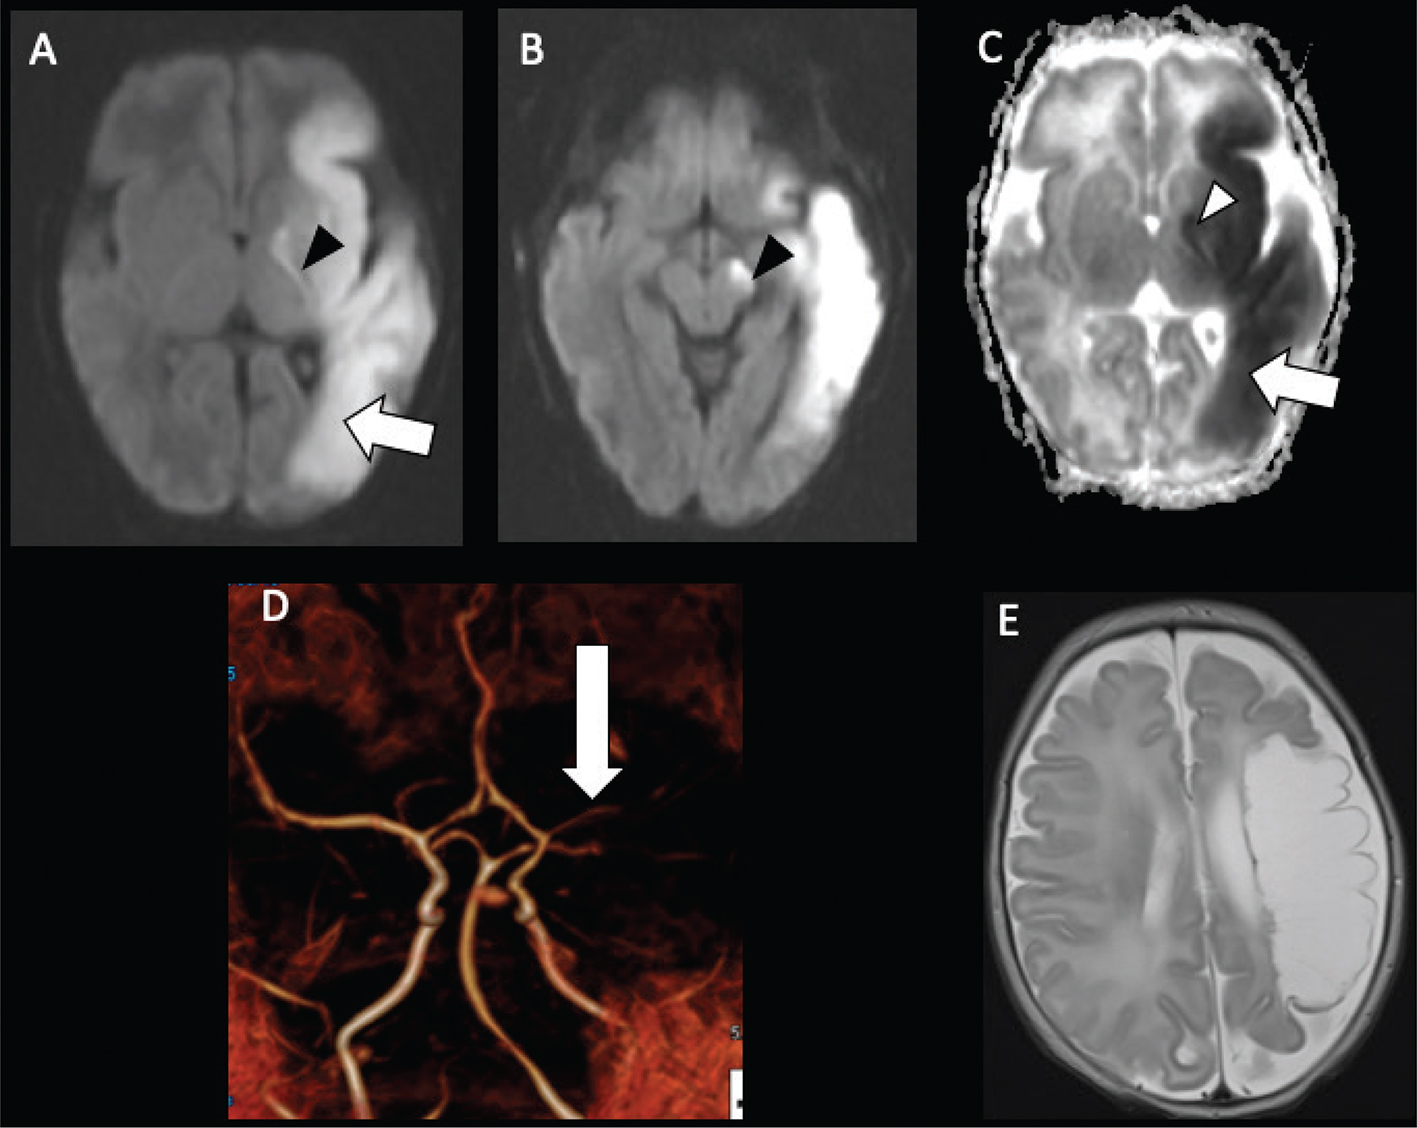

On MRI, acute infarcts demonstrate reduced diffusivity within minutes, exhibiting high signal on DWI and low computed diffusivity on ADC maps (Figure 5) (46). Diffusivity remains reduced for about 6 days, peaking at about 3 days, before pseudonormalization occurs, with diffusivity then increasing to above normal by the second week (4750). Timing of DWI changes can be affected by the age of the patient, size of the stroke, and how quickly collateral blood flow is recruited. DWI also detects early or pre-wallerian degeneration in infants (also referred to as “acute network injury”), characterized by injury to the antegrade white matter tracts following acute infarct and manifests as reduced diffusivity in white matter pathways affected by the infarction within a few days of the injury (Figure 5) (51). Common pathways affected by acute network injury include the corpus callosum, thalamus, and descending corticospinal tract. When seen along the corticospinal tracts, acute network injury is highly predictive of poor motor outcomes (52, 53).

Fig 5

Figure 5. Acute neonatal arterial ischemic infarction in a three-day-old girl with seizures. Axial DWI (A) and (B), and axial ADC (C) images show extensive area of reduced diffusion in the left MCA territory (arrows). Arrowheads (A, B, C) indicate pre-Wallerian degeneration in the posterior limb of the internal capsule and left cerebral peduncle along the corticospinal tract. D. 3D time-of-flight MRA shows abrupt absence of flow in the left MCA (arrow). Axial T2-weighted image (E) at 5-month follow-up shows extensive encephalomalacia and volume loss in the left MCA territory. Case courtesy of Dr. Tamara Feygin, Department of Radiology, Children’s Hospital of Philadelphia.

Perfusion imaging is not routinely used in neonatal stroke for technical reasons––dynamic susceptibility contrast-enhanced (DSC) imaging requires a large, generally power-injected contrast bolus and noncontrast arterial spin labeling (ASL) perfusion is technically challenging in neonates in part due to the faster heart rate––and because it does not presently alter patient management in most cases, although paradigms for use of neonatal perfusion are emerging (19). ASL can be used to assess perfusion without the need for intravenous contrast, with pseudocontinuous tagging schemes (pCASL) and ideally flexible prescription of post-label delays preferred (66). Compared to the core and penumbral hypoperfusion seen in older children and adults, neonates often demonstrate hyperperfusion within the region of decreased ADC (Figure 7), with little evidence of adjacent hypoperfusion, which may be related to reperfusion or seizure-associated neuronal hyperexcitability (67). Hypoperfusion may be more common in venous stroke (67).

Fig 7

Figure 7. Neonatal arterial ischemic infarction. DWI (A) demonstrates reduced diffusion in the right PCA territory (white arrow), from acute infarct, as well as the callosal splenium (white arrowhead), representing acute network injury, with increased perfusion on Arterial Spin Labeling (ASL) perfusion (black arrow) (B). Case courtesy of Dr. Tamara Feygin, Department of Radiology, Children’s Hospital of Philadelphia.